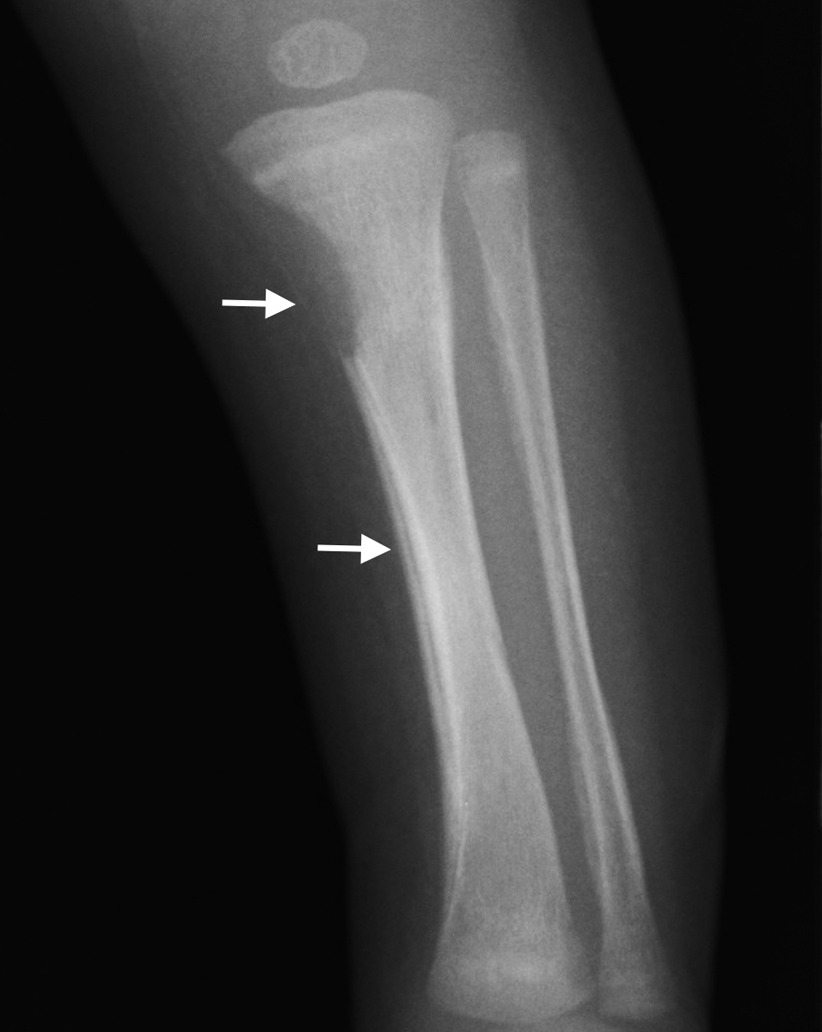

• 골연골염 (Osteochondritis): 손목,팔꿈치, 발목, 무릎에 발생. 통증으로 인한 활동 제한 (Parrot 가성마비).

• 골막염 (Periostitis): X-ray에서 골막 반응 관찰.

• Wimberger 징후: 상부 경골(tibia)의 골간단 내측부 파괴.